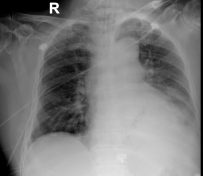

10月14日胸部CT检查:

10月15日

10-25胸部X线